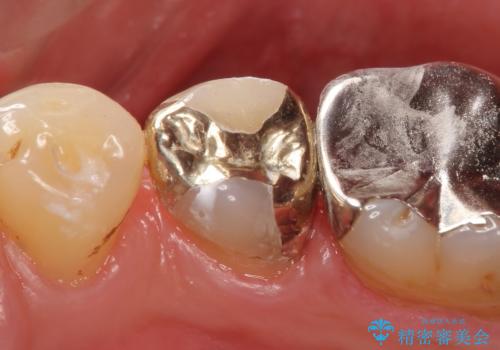

- 右下5番目の歯がしみるので診て欲しいといらっしゃった方の症例です。

古い銀歯及び虫歯を除去後、PGA(ゴールド)インレーによる修復を行いました。

ゴールドは化学的な安定性が高いため変色や腐食がほとんどなく、アレルギーなども起こりにくい人体に優しい素材です。

また硬さも天然歯に近いため周囲の歯への影響も少なく、さらに適合もよいため虫歯の再発も少ない、とても補綴に適した材料です。